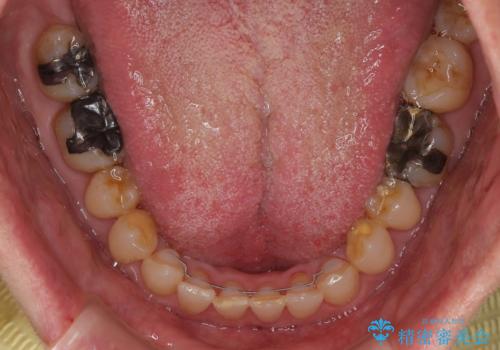

ディープバイトが改善され、睡眠時の食いしばりも緩和され、顎への負担が軽減されました。